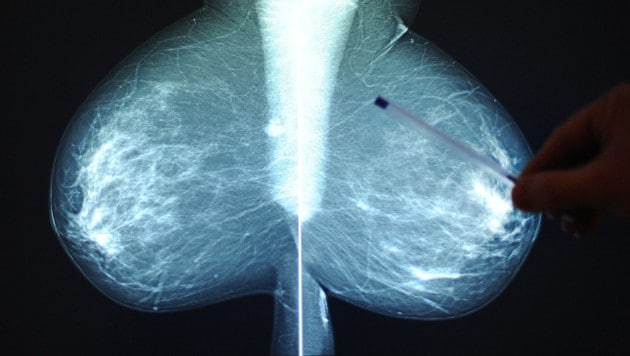

Mammografien sind die häufigsten bildgebenden Früherkennungsuntersuchungen – in diesem Fall auf Brustkrebs. Doch sie könnten durch neueste Forschungen noch einen bedeutenden Zusatznutzen erhalten: Warnungen vor Atherosklerose. Ein in den USA entwickeltes KI-System kann Verkalkungen in den Arterien der weiblichen Brust quantifizieren und auf mögliche Probleme hinweisen.

Im Fachmagazin der Europäischen Gesellschaft für Kardiologie (ESC; „European Heart Journal“) ist vor Kurzem eine wissenschaftliche Arbeit erschienen, welche die Bedeutung der Mammografie deutlich erhöhen könnte.

Bei Frauen oft nicht diagnostiziert

„Herz-Kreislauf-Erkrankungen werden bei Frauen häufig nicht diagnostiziert und unzureichend behandelt. Die automatische Quantifizierung der Brustarterienverkalkung (BAC) in der Screening-Mammografie kann Frauen mit einem erhöhten Risiko für Herz-Kreislauf-Erkrankungen identifizieren“, schrieben Theodorus Dapamede (Abteilung für Radiologie der Emory Universität in Atlanta/US-Bundesstaat Georgia) und seine Co-Autoren.

Die Wissenschafter werteten die Daten von 123.762 Frauen aus, die sich in zwei US-Gesundheitssystemen (Emory Healthcare und Mayo Clinic) Mammografie-Untersuchungen zur Brustkrebs-Früherkennung unterzogen hatten. Mit einem KI-unterstützten System wurden Verkalkungen der Arterien der untersuchten Brust quantifiziert und in vier Kategorien eingeteilt: keine Verkalkungen, leichte Verkalkungen (bis zehn Quadratmillimeter), mittelgradig (zehn bis 25 Quadratmillimeter) und schwer (mehr als 25 Quadratmillimeter).

Zusätzlicher Warnhinweis

Der Beobachtungszeitraum betrug sieben Jahre. In dieser Zeit wurden aufgetretene Herzinfarkte, Schlaganfälle, chronische Herzschwäche und Todesfälle infolge von Herzerkrankungen mit den Daten aus den Mammografien korreliert. Die akuten Ereignisse werden in der Fachsprache der Kardiologen als MACE – schwere Herz-Kreislauf-Ereignisse – zusammengefasst.

Die Ergebnisse sprechen dafür, dass eine Mammografie mit der Auswertung der atherosklerotischen Veränderungen in den Arterien der Brust einen zusätzlichen Hinweis auf ein Herz-Kreislauf-Risiko geben kann: Leichte Verkalkung bedeutete im Vergleich zu keinen Gefäßveränderungen ein um 28 bis 32 Prozent erhöhtes Risiko für solche potenziell lebensgefährlichen akuten Erkrankungen. Moderate Verkalkungen steigerten die Gefährdung bereits um 75 bis 79 Prozent. Schwere Verkalkung verdreifachte das Risiko.